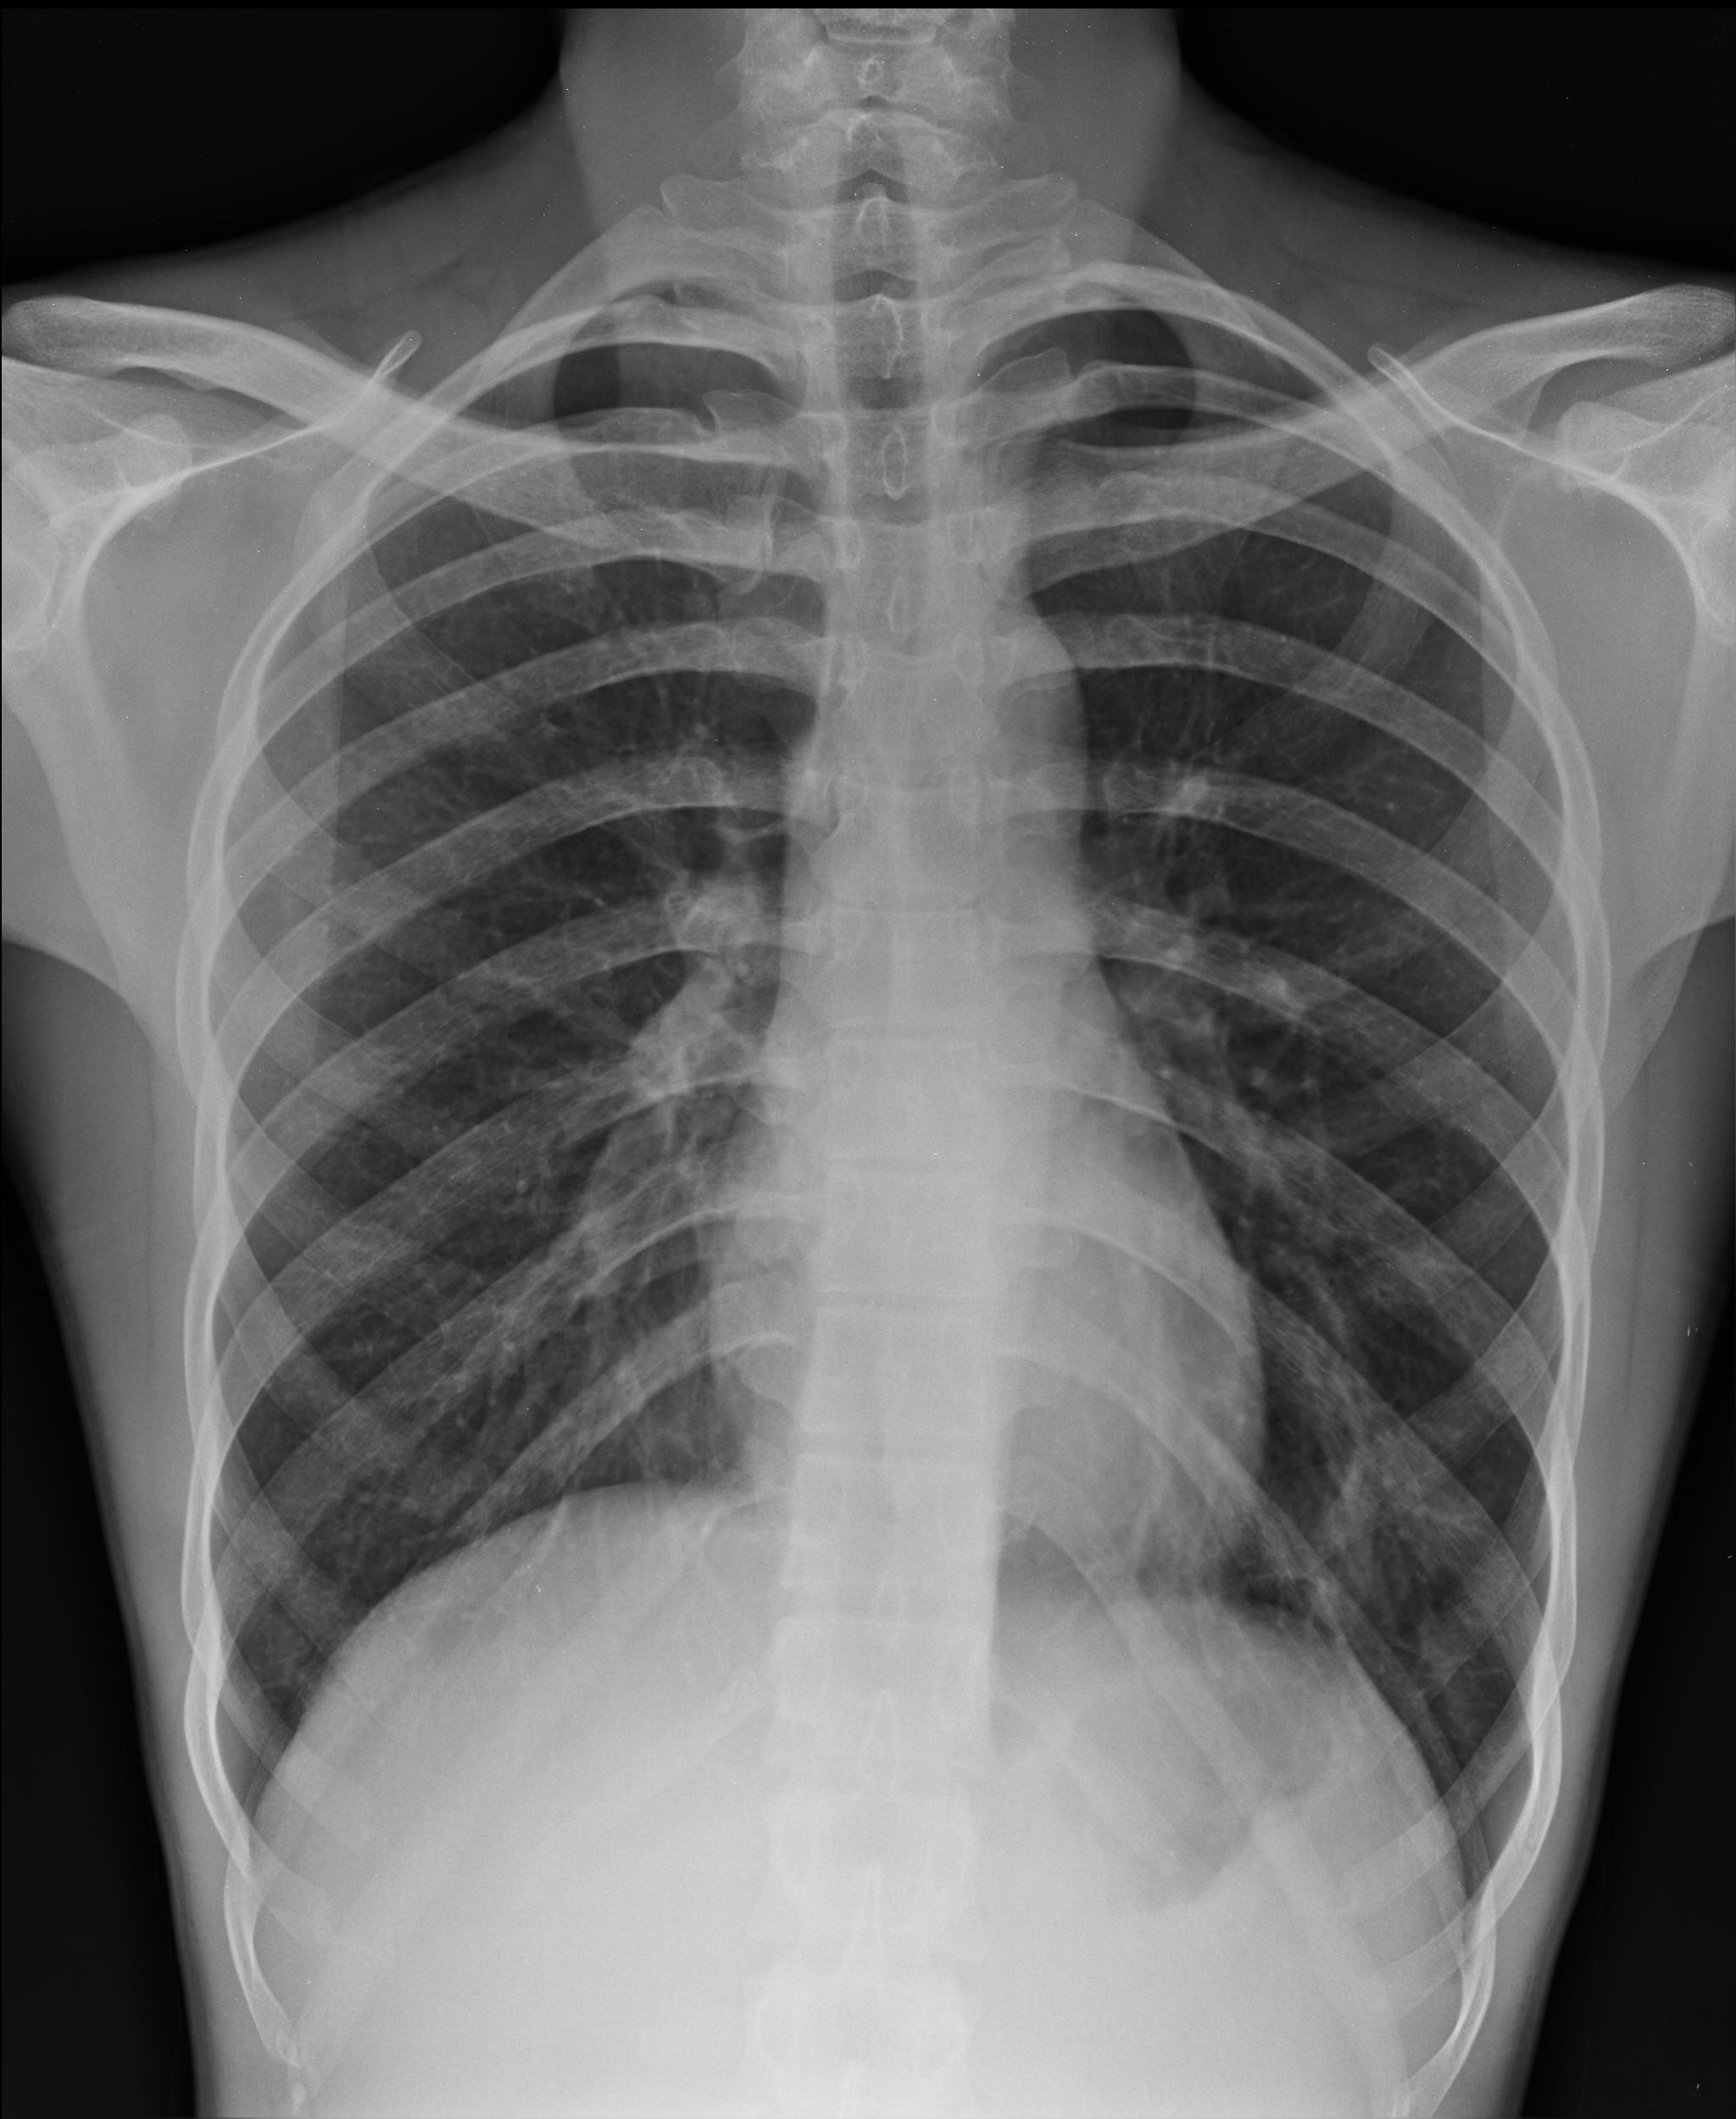

Figure 1:

PA chest x-ray.

The patient ultimately received a 2-view PA/lateral chest X-ray which revealed 2 acute rib fractures on the right side. His vitals remained stable without hypoxia and his pain was well controlled in the Emergency Department with opioids. He was ultimately discharged home without further workup with a prescription for lidocaine patches, methocarbamol, and oral opioids for breakthrough pain. He was also given an incentive spirometer for pulmonary rehabilitation. On 1-month follow up, his pain is improving, and he has not had any new fevers, shortness of breath, or any other symptoms.